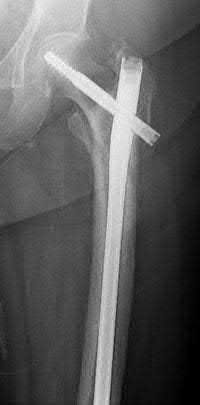

Figure A demonstrates a displaced subtrochanteric femur fracture with an intact lesser trochanter. The pull of iliopsoas on the lesser trochanter as well as the intact external rotators and gluteal musculature results in the the proximal fragment being in a flexed and externally rotated or abducted position (the most common post operative deformity). Reduction manuevers must be biologically friendly but also counteract the flexion/abduction moment. Lundy's review article discusses evaluation and treatment of subtrochanteric fractures. The review article details the various implants often used which include 95 degrees plates, femoral reconstruction nails, or trochanteric femoral nails with interlocking options. Lundy's article discourages the use of the 135 degree screw and side plate combo due to high failure rates in these fracture patterns. Bedi et al also review treatment of these fractures and discuss common

problems of malunion, nonunion, and implant failure. The article reviews reduction techniques that are soft tissue friendly, as well as the use of appropriate implants in these fracture types.